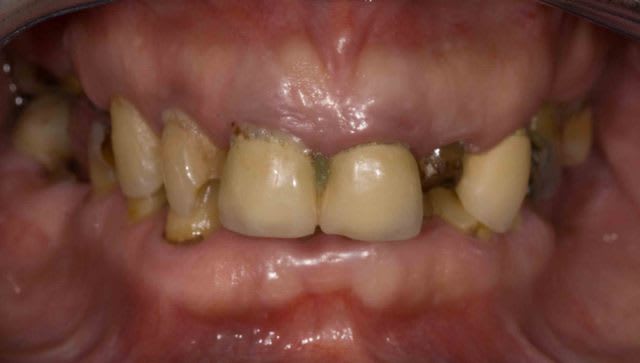

Mais la, apres 1 an de traitements reguliers, entre les lambeaux d'assainissements, les élongations coronaires et les reprises de traitements pourrave j'ai enfin BOUCLE CE CAS !

A l'origine le patient ne voulait surtout pas touché aux dents encore " saine" car il les trouvait bien.

Pour l'egression des dents mandibulaire le patient ne voulait SURTOUT pas toucher au dents encore "saines" .

"Chaques fois qu'on ma touché une dent j'ai eu un probleme donc si elles n'ont rien touchez les pas svp "dixit le patient. En augmentant la DV de 4 mm j'ai pu eviter les meulages.